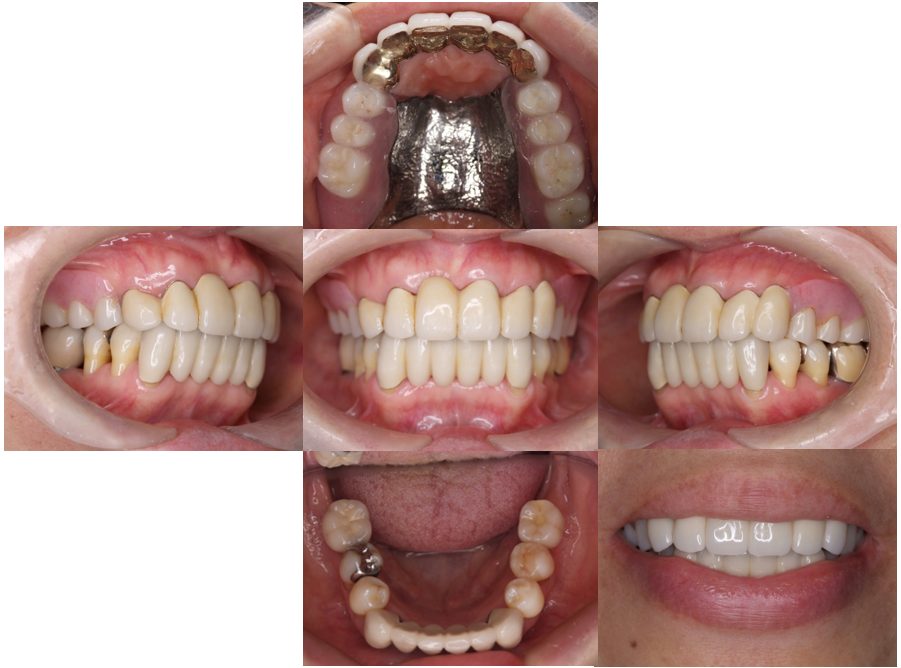

矯正治療・インプラント治療・セラミック治療・金属床(部分入れ歯)の症例紹介(三隅歯科クリニック)

三隅 賢祐(三隅歯科クリニック)

症例詳細

| 主訴 | 50代女性 以前いれた入れ歯が合わなくて使っていないので、しっかり噛めるようになりたい |

| 治療内容 | 矯正治療、インプラント治療、セラミック治療、金属床(部分入れ歯)を行いました。 |

| 治療費 | 4,200,000円(税込み) |

| 治療期間 | 2年(矯正治療期間 1年) |

| 治療回数 | 50回 |

| 想定されたリスク | 重度の歯周病で臼歯部の歯槽骨がかなり吸収していたため、インプラントが脱落するリスクがありました。 |